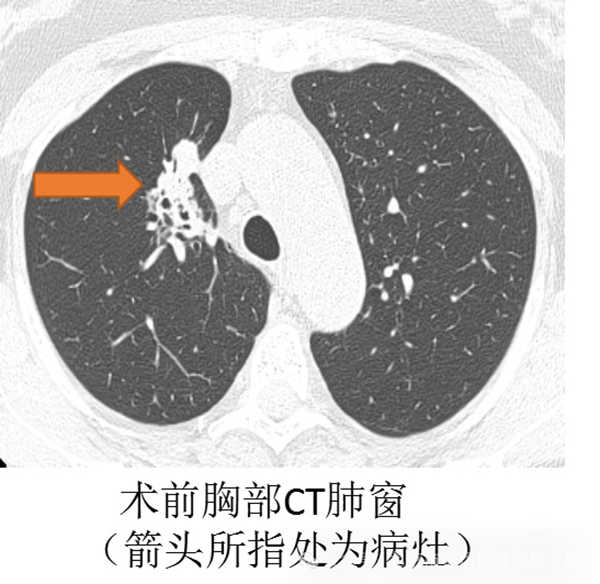

体检完毕,接着继续就诊,做完了胸部增强CT,但还是不能明确良恶性,最终还是需要病理明确,现在的活检方式多样,常用的有CT引导下肺穿刺,不过她的病灶沿着气道分布,CT引导穿刺极有可能穿入邻近的血管、气管,出现气胸、血胸、咯血甚至空气栓塞等危及生命的并发症。

面对患者及家属的期待,垂杨柳医院胸外科团队不敢有丝毫松懈,术中认真观察着气管每一支的异常,并利用胸外科常规开展的EBUS-GS-TBLB技术,应用气管镜下超声小探头,明确探查到右肺上叶前段亚段外侧的病灶,充分进行活检。